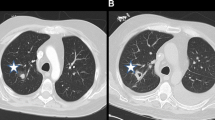

HR CT for pulmonary aspergillosis

The introduction of HR CT has allowed earlier preemptive therapy of many patients by identifying lesions highly suggestive of IFIs in the presence of a positive indirect test. This is particularly true for invasive pulmonary aspergillosis. Spores of Aspergillus sp. usually enter the body through sinuses or respiratory tract infecting them. Aspergillus infects airways resulting in bronchopneumonia in the early stages, which may be normal on chest radiograph. As the disease progresses nodular appearance or patchy consolidations may appear. Aspergillus frequently appears as a single or multiple area of rounded consolidation, which may cavitate. In adults, two key signs exist on HRCT suggestive for invasive pulmonary aspergillosis: the halo sign and the air crescent sign. The halo sign is a ground glass opacity surrounding a pulmonary nodule or mass and represents hemorrhage (Fig. 2). This sign appears transiently in the disease and soon the finding changes to nonspecific findings. The air crescent sign describes the crescent of air that can be seen in invasive aspergillosis. Both the halo sign and the air crescent sign are common and highly suggestive for invasive mold infection in adult patients [30]. However, various retrospective studies demonstrated that these CT findings are less specific in children. In children, other findings including segmental and multilobar consolidation, peripheral infiltrates, multiple small nodules, and larger peripheral nodular masses are common, whereas the halo sign is rarely present [41–44]. The use of HRCT in pulmonary candidiasis is less obvious. Pulmonary candidiasis usually gives small nodular lesions, which do not cavitate [11, 45, 46]. In general, the findings of IFIs in children on HR CT are not specific and may occur in other conditions like bacterial infections or malignancies [10].